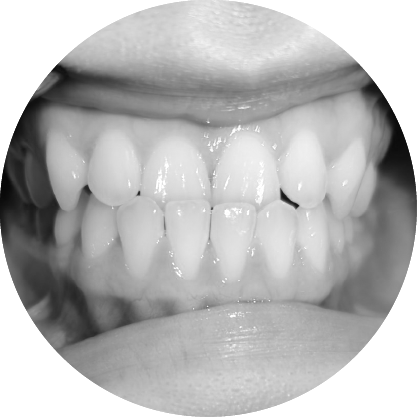

ฟันหน้ายื่น (ฟันสบลึก)

แก้ไขฟันสบลึก เพื่อรอยยิ้มที่สมดุล

ฟันสบลึกเกิดขึ้นเมื่อฟันบนยื่นทับฟันล่างมากเกินไป หากปล่อยไว้โดยไม่รักษา อาจส่งผลต่อรูปลักษณ์และสุขภาพช่องปาก การรักษาทางทันตกรรมจัดฟันมีเป้าหมายเพื่อฟื้นฟูความสมดุลและการทำงานของฟัน เพื่อให้คุณมีรอยยิ้มที่มั่นใจ

ตัวอย่างในชีวิตจริง